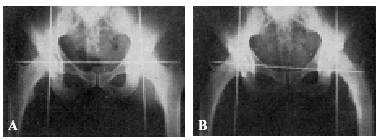

Con la finalidad de simplificar la técnica y ahorrar exámenes radiográficos hemos intentado precisar exactamente la situación topográfica del centro de la cabeza femoral. En 9 cadáveres, en ambos lados, con las articulaciones coxofemorales colocadas en el mismo grado de abducción y rotación interna que en el acto operatorio (distancia entre los talones, de 65 a 70 cm., y rotación interna del pie, de 30 a 40°), hemos hallado que el centro de la cabeza femoral correspondía a la piel de la región inguinocrural a un punto preciso: el lugar de entrecruzamiento de una línea horizontal que pase inmediatamente por el borde superior del pubis con otra línea que siga el trayecto de la arteria femoral por su parte externa (figs. 9, 10, 11 y 12). En dicho punto clavamos verticalmente, hasta que se insinúe en el hueso, una aguja de Kirschner, provista de un mango adecuado que permita hacer presión. La introducción de la aguja mediante un taladro tiene un peligro: el que se enrollen alrededor de aquellas ramas del nervio crural, como hemos podido comprobar nosotros en el cadáver.

Figura 9. Experiencia cadavérica núm. 2. Se ha clavado verticalmente un Kirschner en el lugar de entrecruzamiento de una línea horizontal que pasa inmediatamente por el borde superior del cuerpo del pubis, con el borde externo de la arteria femoral.

Figura 10. Experiencia cadavérica núm. 2. El mismo caso de la figura anterior. Se han colocado dos Kirschner verticales: uno, inmediatamente por encima, y otro, inmediatamente por debajo de la periferia del borde posterior de estos dos tercios de esfera que representa la cabeza femoral.

Figura 11. Experiencia cadavérica núm. 6.

Figura 12. Experiencia cadavérica núm. 6.

Al aplicar dicha técnica en el vivo, hay que tener sumo cuidado de que la línea que pasa por ambas espinas ilíacas anterosuperiores se mantenga perpendicular a la línea xifoidea púbica (véase la fig. 14).

Figura 14. A: radiografía obtenida sin exploración radioscópica previa. Obsérvese cómo el alambre de Kirschner que pasa inmediatamente por encima de la espina del pubis, corresponde, en ambos lados, exactamente a la fosita de inserción del ligamento redondo. El fémur, en ambos lados, está colocado en la misma posición que en el acto operatorio. B: si se bascula la pelvis, y por lo tanto, la línea que pasa por ambas espinas ilíacas anterosuperiores deja de ser perpendicular a la línea xifoidopúbica, deja de tener valor el punto de referencia que preconizamos.